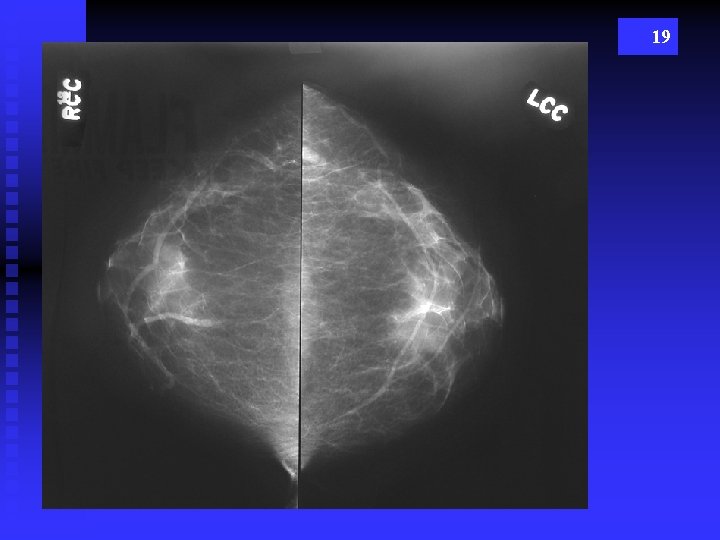

19